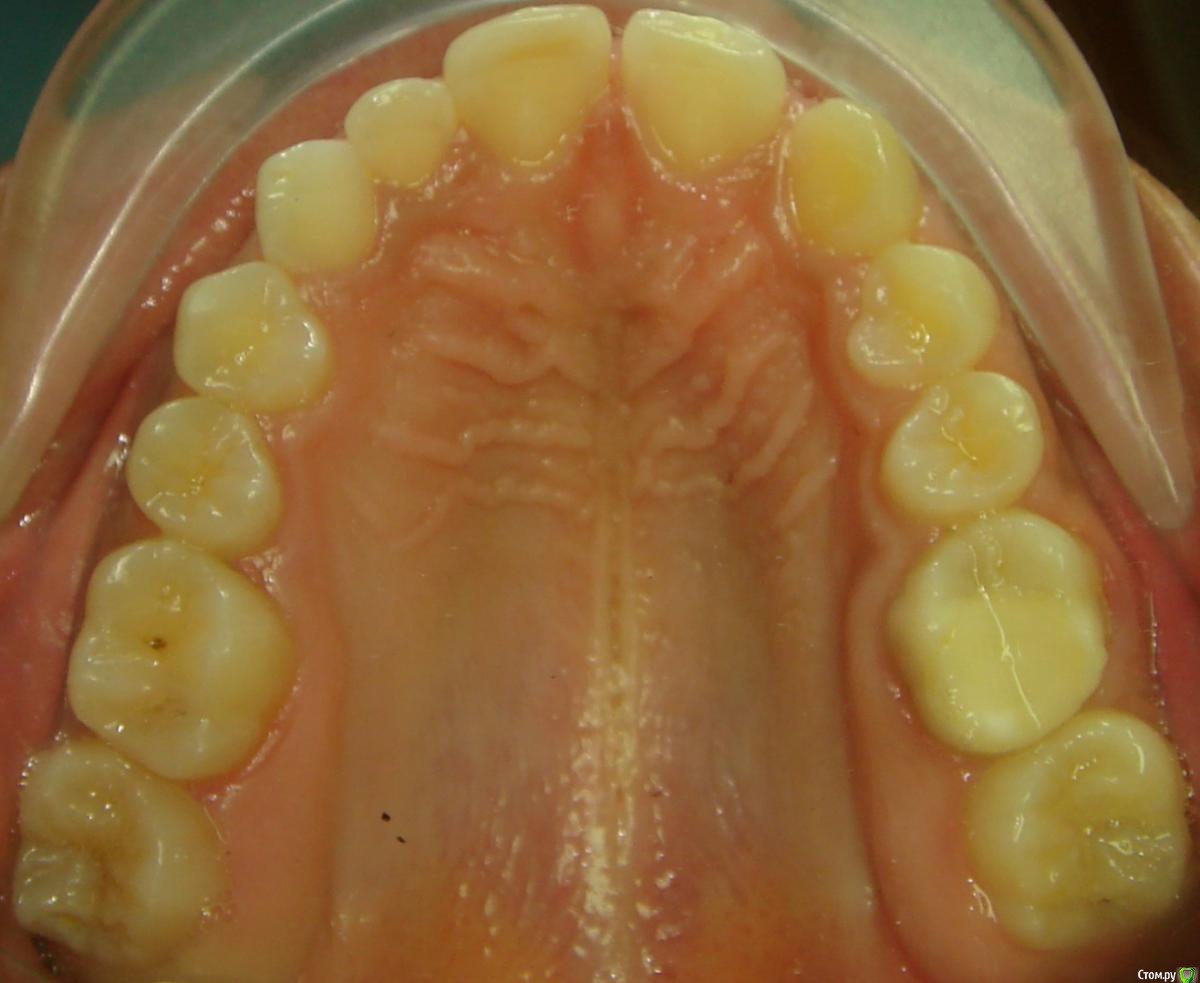

Opdihatop Опубликовано 20 февраля, 2017 Поделиться Опубликовано 20 февраля, 2017 Здравствуйте, коллеги! Вот такой вот случай третьего класса, вертикального роста, множественной первичной адентии и преинтереснейшего 13-го зуба. Девочке 14 лет. Сразу скажу, что вопреки некоторым классикам удалять клык или премоляры мы не будем, будем ставить в дугу, причем на его законное место. Может у кого-то были подобные случаи, поделитесь опытом, будьте добры. Какой план лечения и какая биомеханика тут будут самыми оптимальными? Заранее всем спасибо! Ссылка на комментарий

Opdihatop Опубликовано 20 февраля, 2017 Автор Поделиться Опубликовано 20 февраля, 2017 52, 53 молочные. 12, 22 - адентия. Клык пойдет на место 13. Когда-то на курсе Рафаэля Спены видел подобное, но, к сожалению не зафиксировал на фото. В общем и целом принцип помню. Но тут есть одно огромное НО... 14, 15 началась резорбция верхушек из-за 13 зуба, что видно по КТ. Ссылка на комментарий

Opdihatop Опубликовано 20 февраля, 2017 Автор Поделиться Опубликовано 20 февраля, 2017 (изменено) вот такая штучка еще в кости... Видел, на вид - простая остеомка, так что пугать пациента не буду, передвижению зубов не мешает. а про каких именно классиков Вы говорите? (это я для себя, для развития..) Вот простите, не вспомню, читал монографию какого-то итальянца еще на этапе обучения, так там было сказано вообще их удалять, особенно при транспозиции через ц.л. у ВАшей девочки я бы удаляла восьмерки, ставила винты в подскуловую область , часть зубов назад, а часть - пружинами вперед. создавая место. про клык - здесь конечно по КТ надо смотреть, куда его тащить и как открывать. Возможно лучше вначале открыть место (раздвинуть 5ку и 4ку) а потом клык поставить между ними. Клык станет 4кой а 4ка клыком. (имхо) Подскуловые импланты, это классно, только вот в Украине этих корейцев не продают пока (Диаметра не хватает и длины). Дистализирую пружинами при непрямом анкораже на микроимплантате между 5 и 6. Как я собирался тянуть клык вперед? На 14, 15 ставятся брекеты от нижних премоляров и ставятся они на толстую композитную подушку, которая постепенно утолщается. Таким образом зубы постепенно уходят орально, а их корням придается небный торк, освобождая путь в кости для 13. Затем при помощи компактостеотомии быстро мезиализируется 13, затем 14 и 15 плавно перемещаются назад (хотя 15 это вряд ли коснется... его я планирую перед этим дистализировать). Сам я такое не делал, но видел на курсе. Вот, выпал шанс попробовать. Зачем? Во-первых, научный интерес, во-вторых, родители категорически против ремоделирования коронок зубов... Изменено 20 февраля, 2017 пользователем Opdihatop Ссылка на комментарий